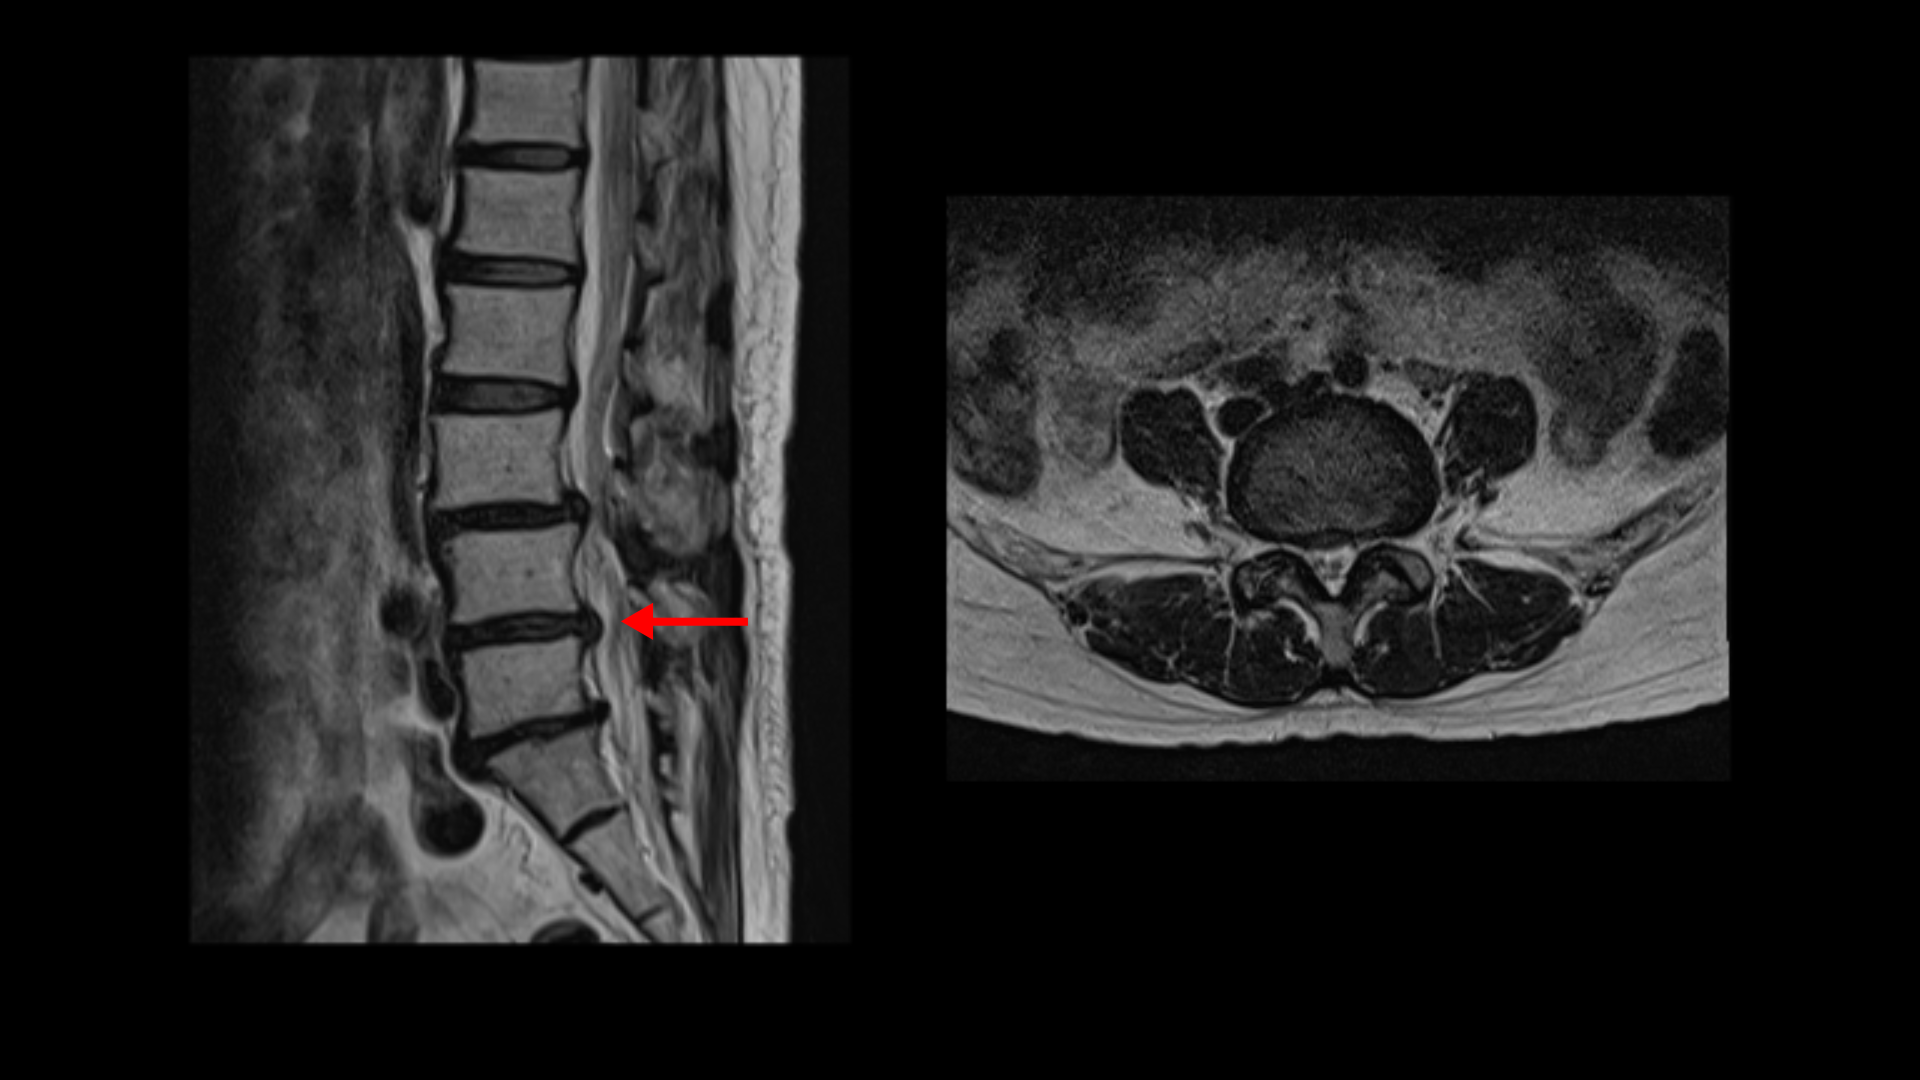

이분 MRI를 보면 3마디에 퇴행성디스크가 밀려 나와 있습니다.

또 3번 4번에는 척추전방전위증이 있습니다.

이 전방전위증 때문에 척추관에 중심성 협착도 있습니다.

4번 5번 디스크가 중앙에서 우측으로 약간 밀려 나와있고

>또 5번 1번에서는 신경이 빠져나가는 오른쪽 추간공이 약간 좁아져 있습니다.

그런데 이분 허리 MRI를 자세히 보면 딱히 신경이 아주 극심하게 눌린 곳도 없습니다.

신경이 조금 눌릴 수는 있어도 심각해 보이지는 않습니다.

신경구멍이 지나가는 길이 여러 가지 퇴행성 변화로 조금씩은 좁아져 있지만 굳이 수술로 특히 여러 마디의 나사를 박는 수술까지 해가며 신경압박을 해소해야 할 정도의 심한 신경눌림은 보이지 않는 겁니다.